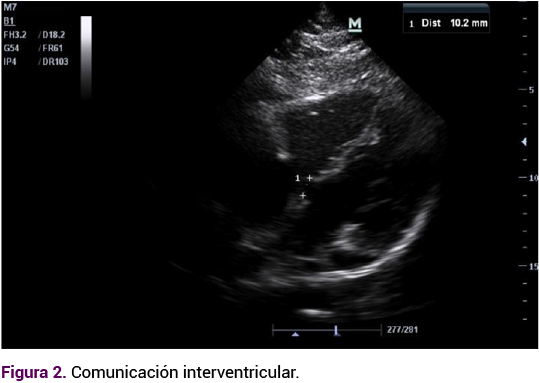

El ecocardiograma transtorácico reportó una comunicación interauricular tipo ostium secundum amplia de 27 mm (Figura 1) y comunicación interventricular subpulmonar de 15 mm (Figura 2), estenosis valvular pulmonar moderada con gradiente de 55 mmHg (Figura 3) ventrículos no dilatados, función sistólica preservada, presión sistólica ventricular ligeramente aumentada del ventrículo sistémico. Por lo anterior, se sugirió hipertensión pulmonar no grave, dextrocardia y situs inversus. Se confirmó el diagnóstico de trasposición congénitamente corregida de las grandes arterias.

Figura 1. Ecocardiograma con comunicación interauricular amplia tipo ostium secundum, con medición aproximada en corte diagnóstico.